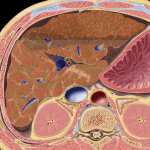

Xơ gan (Cirrhosis) là một bệnh gan mạn tính được đặc trưng bởi sự thay thế mô gan bằng mô xơ, sẹo và sự thành lập các nốt tân sinh, dẫn đến mất chức năng gan. Như vậy xơ gan không phải là một bệnh riêng biệt mà là một hội chứng bệnh lý, là hậu quả cuối cùng của quá trình tổn thương tế bào gan. Xơ gan có sự kết hợp của 3 quá trình tổn thương: Tổn thương tế bào gan – Tăng sinh tổ chức liên kết – Tái tạo tế bào gan…